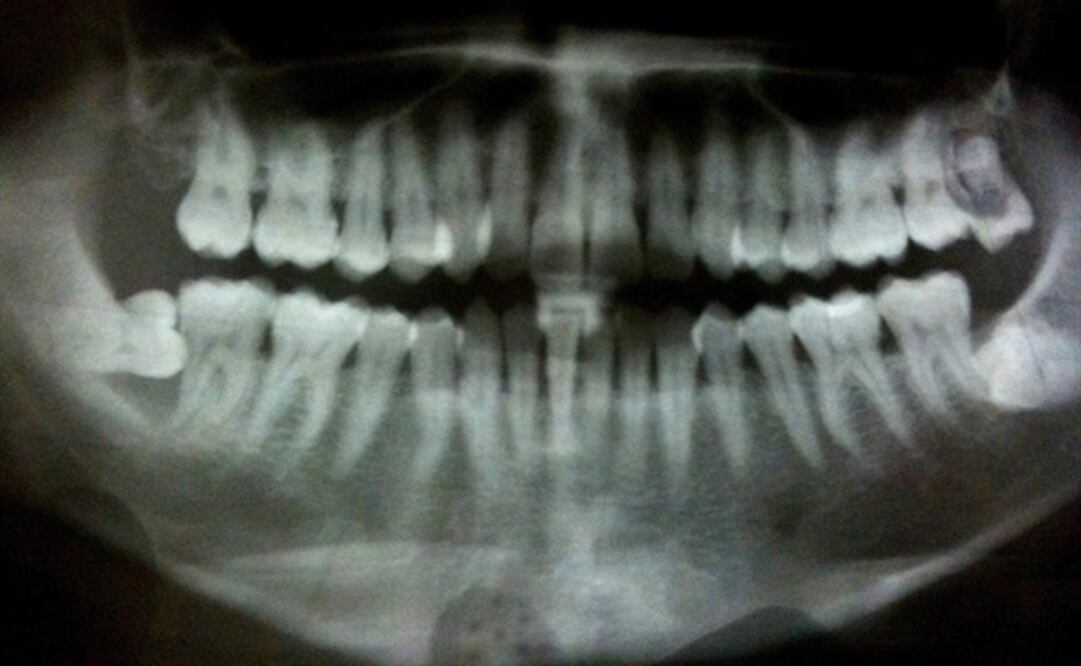

Investigadores de la Universidad de Helsinki (Finlandia) y el Instituto Karolinska de Estocolmo (Suecia) aseguran que la salud oral también puede tener un papel importante en la prevención del cáncer, tras observar que las bacterias que provocan la periodontitis pueden estar implicados en la aparición de los tumores pancreáticos .

En un estudio, publicado en el último número de la revista British Journal of Cancer , han observado por primera vez la existencia de un mecanismo a nivel molecular por el que las bacterias asociadas con la periodontitis, las treponema denticola (Td), influye en el desarrollo de estos tumores.

En concreto, encontraron un factor de virulencia primario de estas bacterias, la proteinasa Td-CTLP, que también tiene lugar en tumores malignos del tracto gastrointestinal, como el cáncer de páncreas .